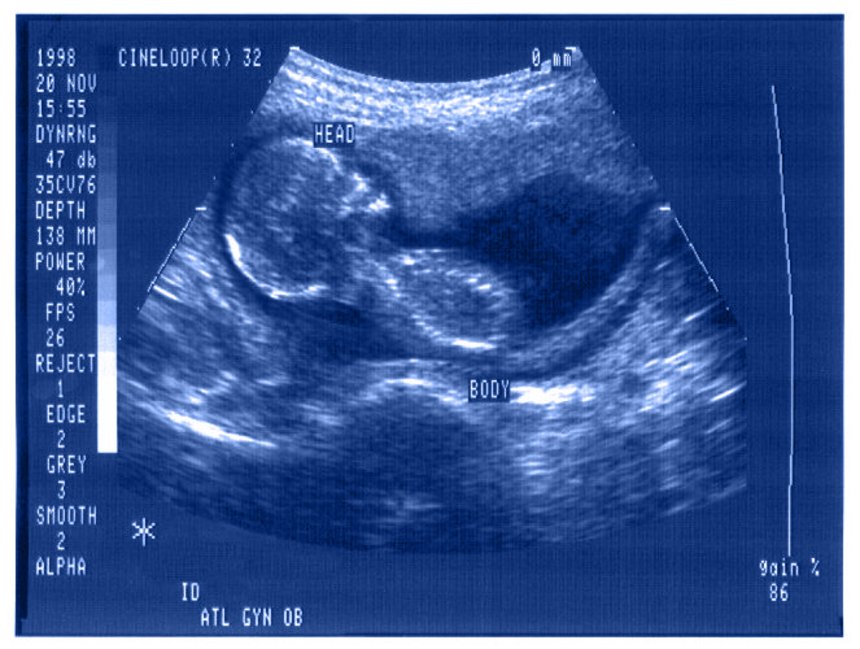

Dwa ujęcia relacji kobieta ciężarna, a płód - model kompleksowy i dualny. W pierwszym z nich, kobieta i płód są traktowani przez lekarzy jak jeden pacjent, natomiast w drugim także fazom prenatalnym życia ludzkiego przyznaje się moralny status samodzielnego pacjenta. W praktyce lekarskiej i w świadomości społecznej pierwszy model zostaje wyparty przez drugi. Opowiemy o mechanizmach upodmiotawiania płodu charakterystycznych dla współczesnej kultury popularnej, widocznych na przykład w takich filmach, jak Bridget Jones 3 (reż. Sharon Maguire, 2016), czy we wcześniejszych utworach (I kto to mówi, reż. Amy Heckerling, 1989). Dodatkowym kontekstem będą praktyki społeczne, takie jak umieszczanie ultrasonograficznych obrazów płodów pośród pamiątkowych fotografii czy w portalach społecznościowych. Będziemy starali się prześledzić powiązania między tymi zjawiskami, ich historyczne uwarunkowania i możliwe konsekwencje (uprzedmiotowienie kobiety wynikające z upodmiotowienia płodu, wymaganie moralnych poświęceń od ciężarnej, uczynienie z płodu ważnego uczestnika i bohatera kultury popularnej).